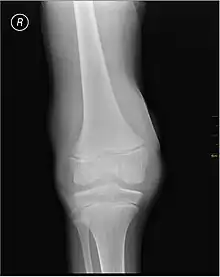

X-ray of Hemarthrosis X-ray of Hemarthrosis